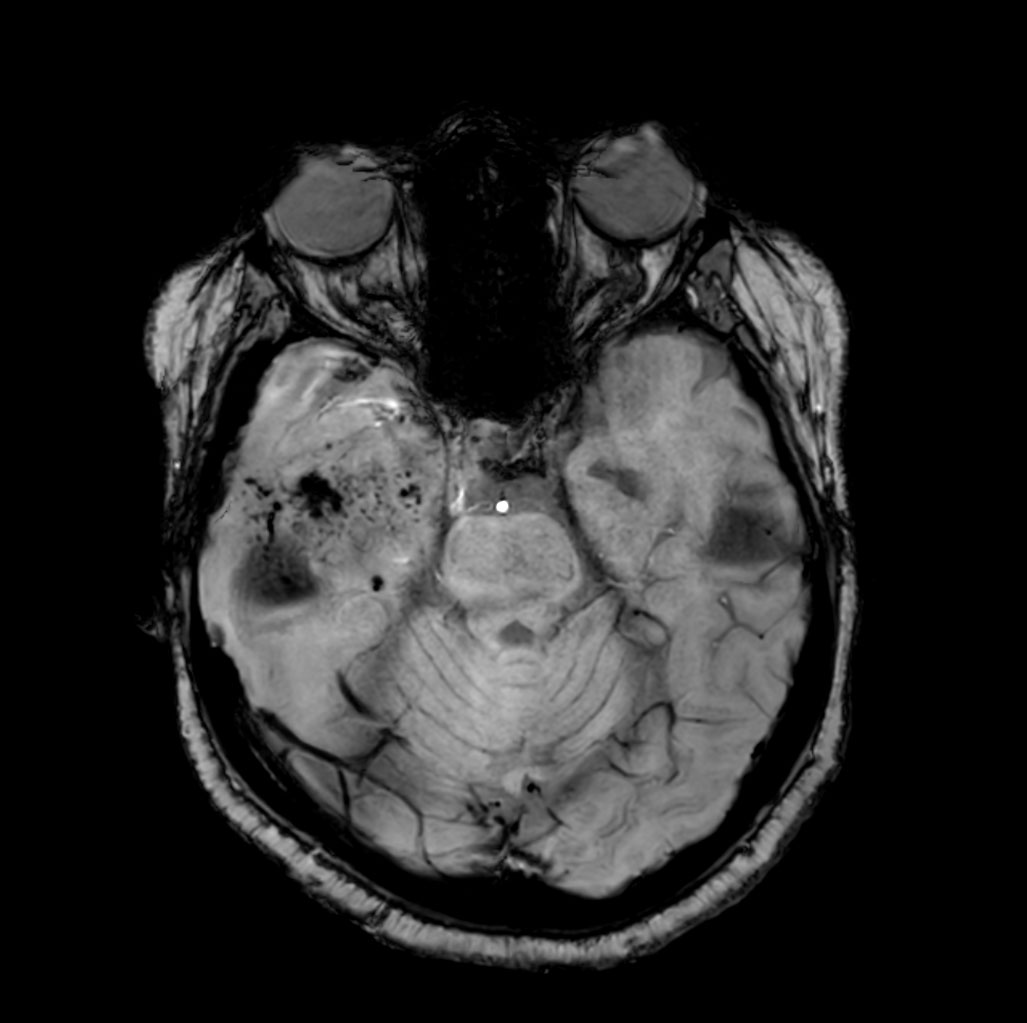

Axial SWIp

-